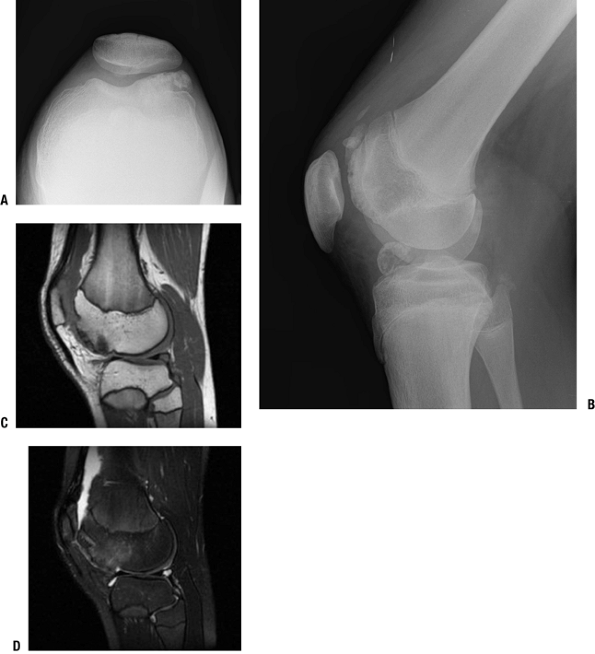

Figure 21-18

Dysplasia epiphysealis hemimelica (Trevor disease). A 14-year-old boy

with atraumatic knee pain and locking and epiphyseal osteochondroma.

Sunrise (A) and lateral (B) views of the knee show an osseous

excrescence extending from the anterior aspect of the lateral femoral.

Multiple osteochondral fragments project in the joint. Note the

elongation of the inferior pole of the patella in response to

chronically abnormal patellofemoral mechanics. Sagittal T1-weighted (C)

and T2-weighted (D) images through the lateral femoral condyle show the

lesion at the anterior aspect of the femoral condyle, with cortical and

medullary continuity with underlying bone. -

It essentially consists of an epiphyseal osteochondroma that protrudes into the joint space.

-

The medial side of the epiphysis is most commonly affected.

Radiologic Findings (Fig. 21-18)

The gross anatomy is of an exostosis,

projecting and contiguous to the subchondral surface, covered by

cartilage. The radiograph shows an abnormal projection of normal bone

arising from the subchondral surface. Arising in childhood, the

abnormal forces of this focal projection may cause secondary local

changes in the adjacent articular structure. -

Magnetic resonance imaging will show the

continuity of the base of the exostosis with the subchondral bone as

well as abnormal signal in the cartilage cap in both the T1-and

T2-weighted images.